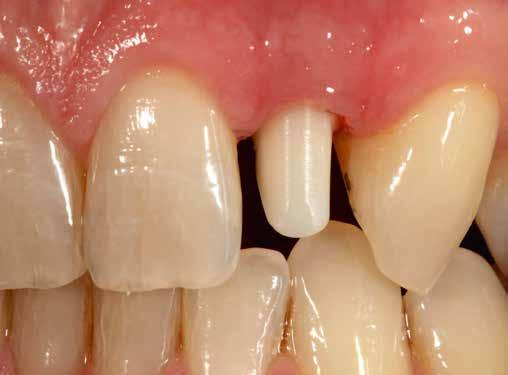

Elhagyott frontfogak, megtámadott parodoncium: a páciens kiindulási helyzete több mint nehéznek bizonyult. Yuki Momma és dr. William C. Heggerick, szerzőink, bemutatják, hogyan állítható helyre a harmónia a négy frontfog ellátásával.

A felső frontfogak állapota elhanyagolt, a parodontális struktúrák részben erősen károsodottak, VMK korona az 12 zónában, az ínyszél szürke, fekete approximális háromszögek… vörös-fehér esztétikáról nem is beszélhetünk (1. kép). Így jelentkezett a hölgypáciens a Weston Dental Specialists Group rendelőben. Elvárásai magasak voltak. A defektusok kezelését, a gingiva lefutásának korrigálását kívánta. Gyorsan világossá vált, hogy a megoldást csak a négy frontfog teljes kerámiakoronával való ellátása jelentheti. A jelen eset bemutatja, hogy az IPS e.max ZirCAD Prime segítségével hogyan lehet tiszta, tetszetős és esztétikus mosolyt létrehozni.

1. kép: Kiindulási helyzet.

A kialakítás tervezése

A páciens aggodalmas volt, hogy ne kapjon túl nagy és szögletes koronákat. A vele folytatott megbeszélések során viaszmintázat, majd annak alapján kulcs készült a mock-uphoz. Ennek segítségével az újonnan készülő pótlás formáját közösen, egyértelműen határozhattuk meg (2. kép).